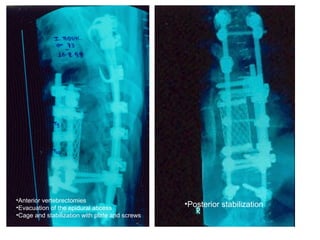

•Anterior vertebrectomies

•Evacuation of the epidural abcess

•Cage and stabilization with plate and screws

•Posterior stabilization

T.B.C.

Thoracic spine